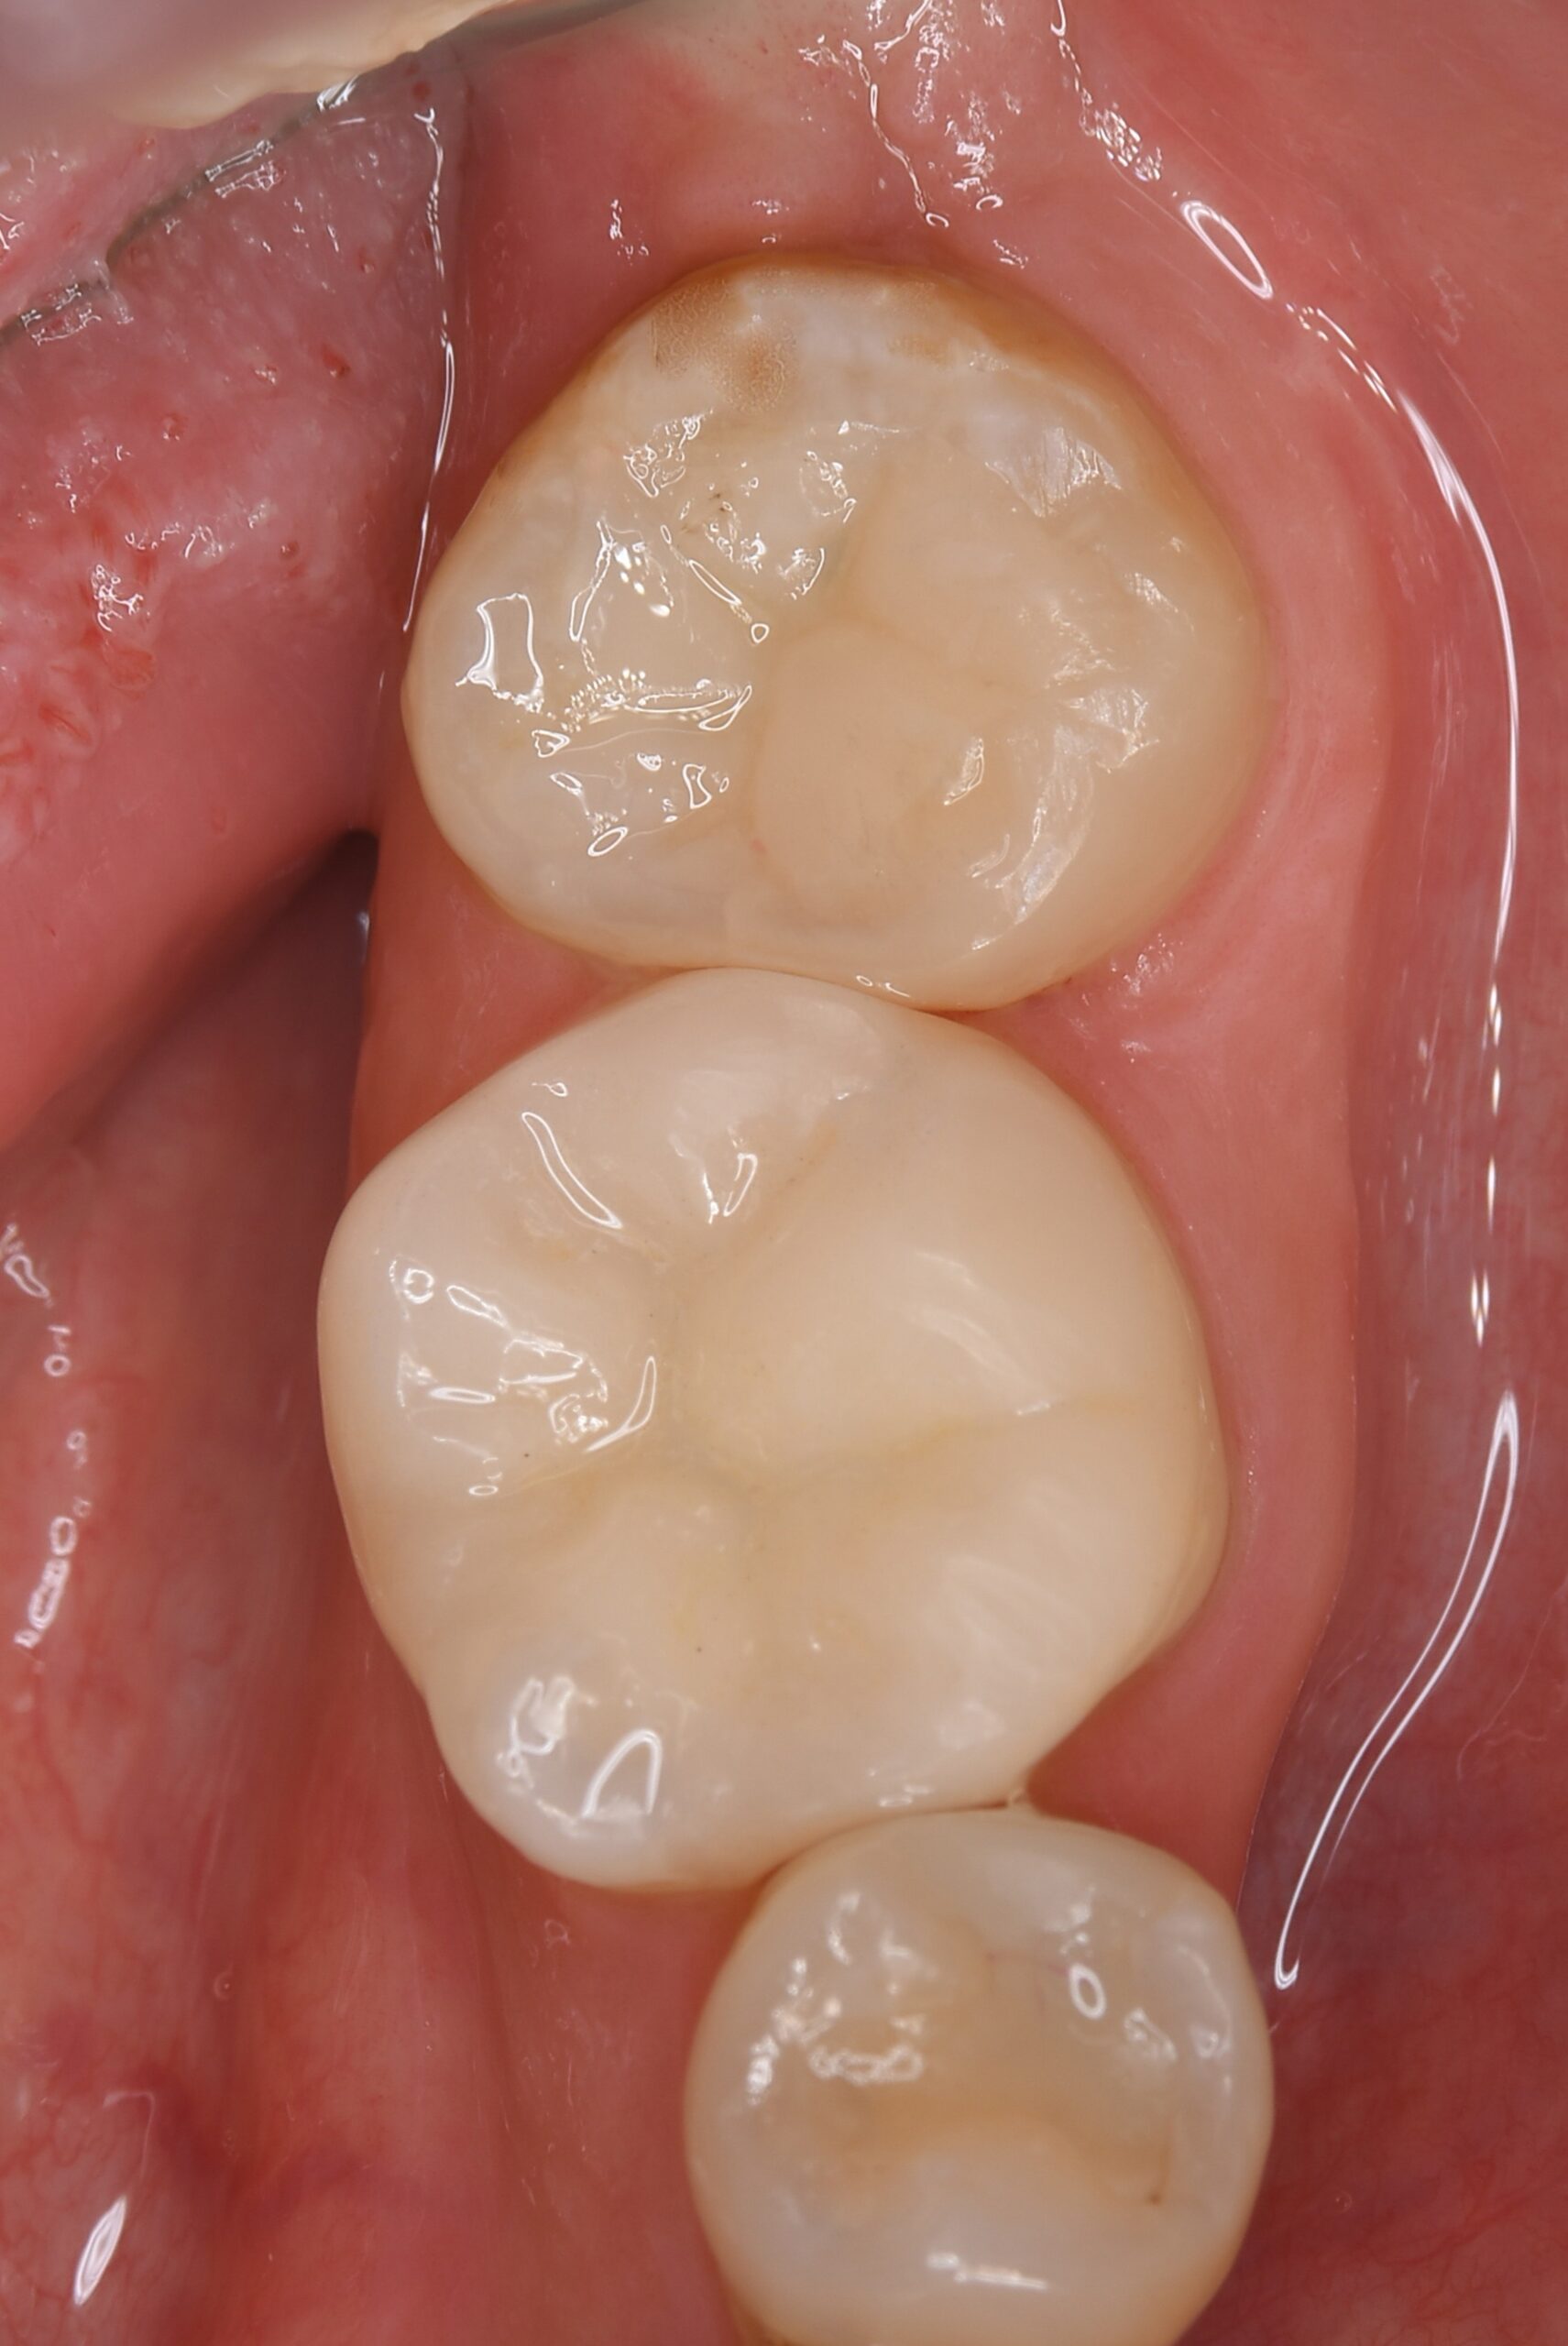

症例4

右下親知らずを右下第二大臼歯へ移植

| 患者様データ | 20代 女性 |

| 来院時の主訴 | 「右下奥歯で噛むと痛い。」 |

| 医院の診断 | 歯根破折 |

| 通院期間 | 6か月 |

| 来院回数 | 10回 |

| 治療費 | 総額:255,000円(税抜) 【内訳】 歯牙移植150,000円、ファイバーポストコア20,000円、セラミック治療85,000円 |

| リスクと副作用 | ①根管治療歯は長期的には破折するリスク ②長期的なメインテナンスが必要 ③歯根の外部吸収 |

| ここがこだわりのポイント!☝ |

抜歯が必要になった際に余っている親知らずがあれば移植歯として利用することができます。 術前に撮影したCT画像から3Dプリンターを用いて親知らずのレプリカを作製することで、親知らずが乾燥することを防ぎ、成功率が上がるよう努力しています。 |